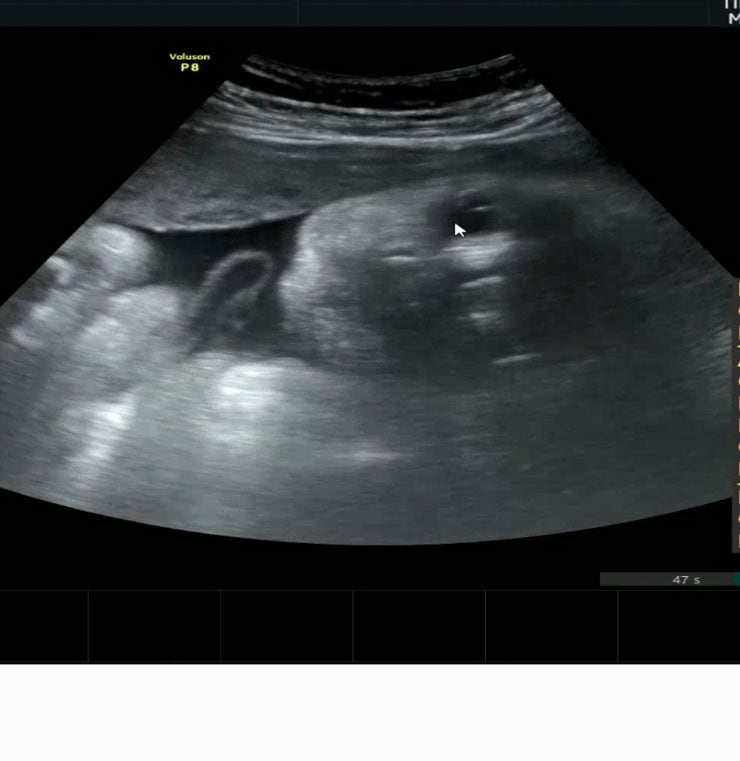

32w 0d 정기검진

어느덧 32주 30주에 1.7이더니 2주만에 2키로 돌파하신분 머리크기 주수보다 2주 크신분.. 형은 머리 작았...